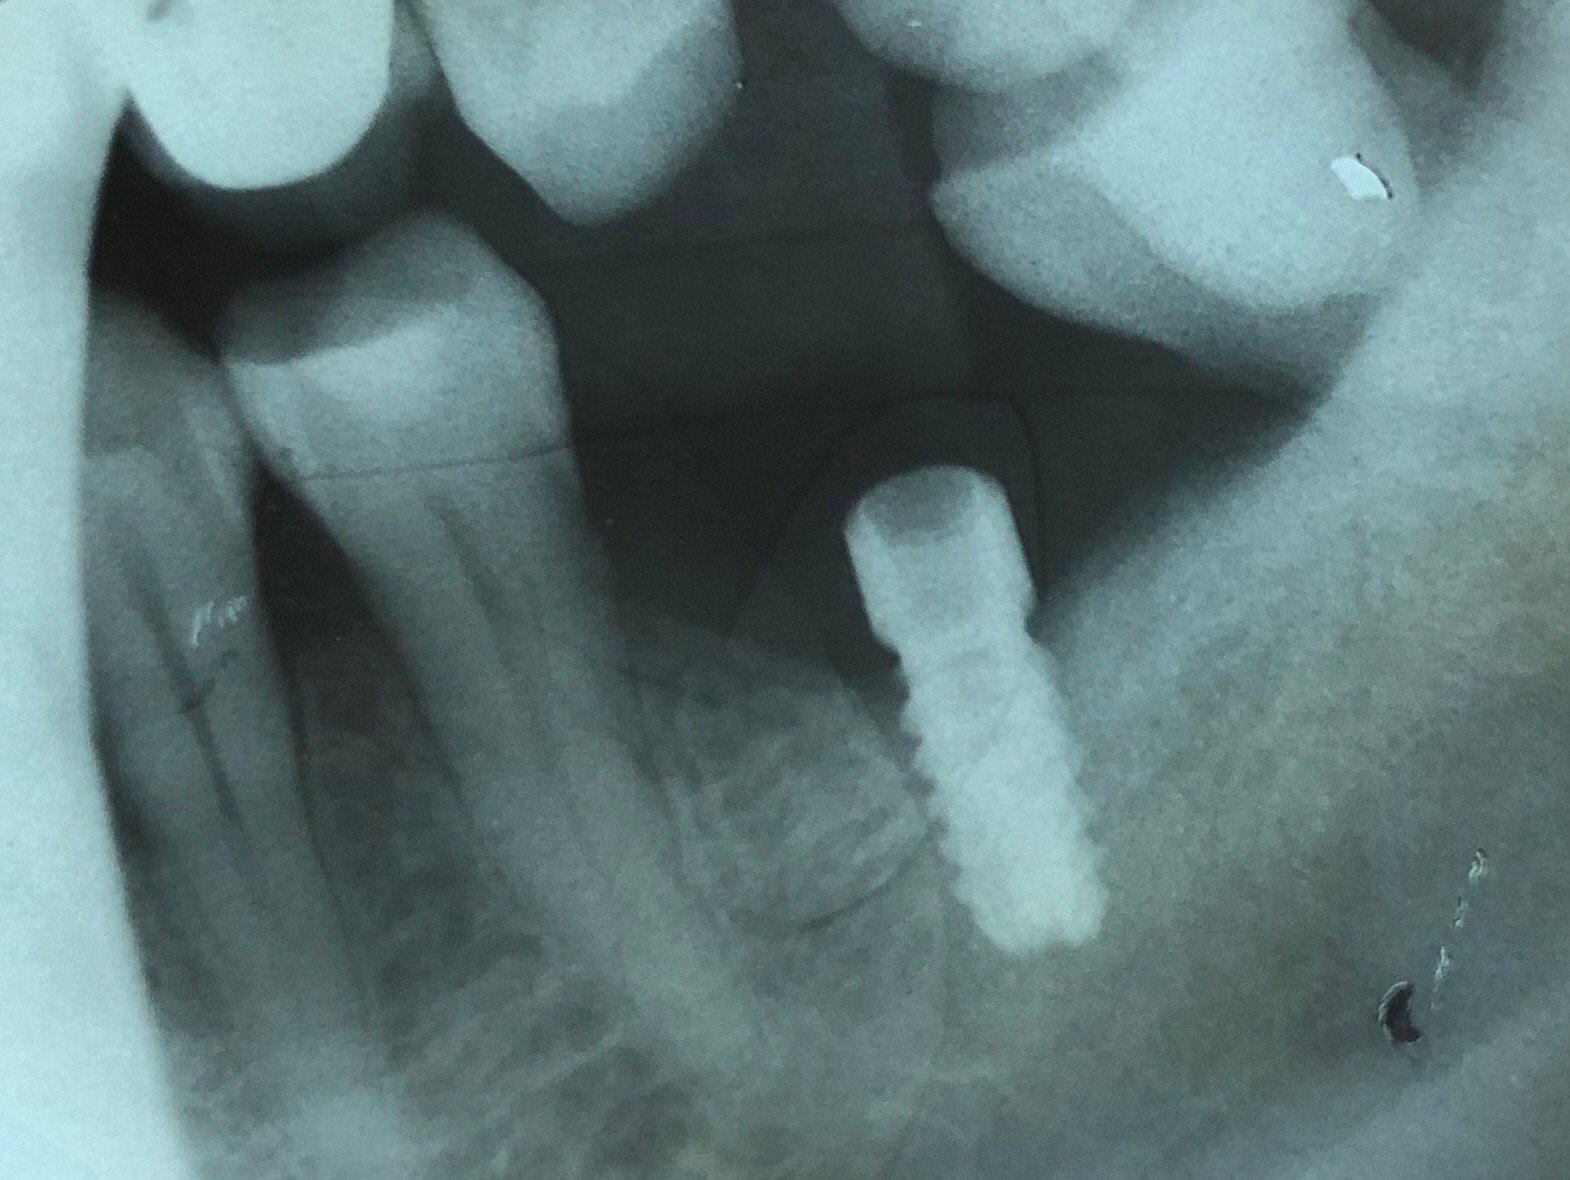

¿Podrían ayudarme a identificar el implante de la 36 ( mas mesial)?